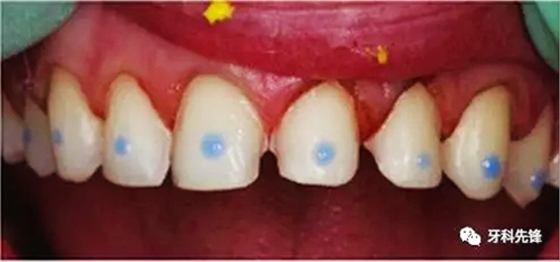

6.牙面處理

7.粘結(jié),需把牙列上貼面同時就位,同時用極小的粘結(jié)劑粘結(jié)固位每個貼面后,才開始逐個粘結(jié)。